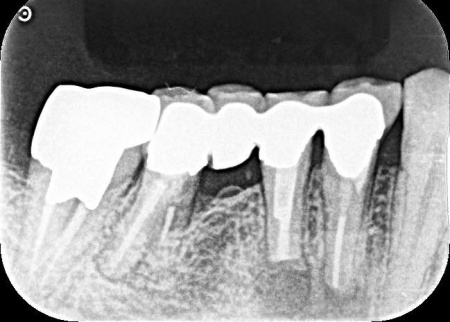

歯やあごの骨の状態を詳しく調べるためレントゲン検査を行った結果、右下の奥歯2本(第2小臼歯、第1大臼歯)は、歯根が縦方向に割れている可能性が高いと考えられました。

しかし、レントゲン画像だけでは歯根の状態を正確に判断することはできません。